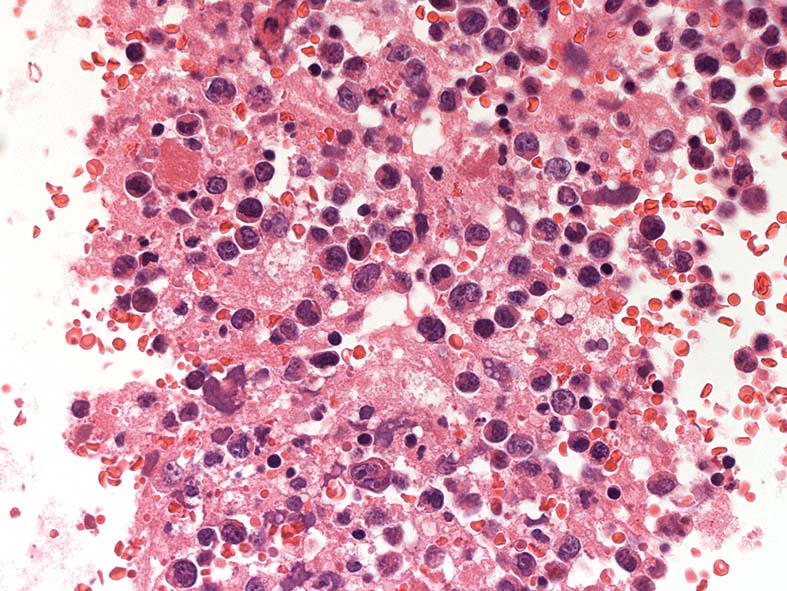

心タンポナーデの診断で心嚢液穿刺ドレナージ. 心嚢液内に多数の異型細胞増加が認められた.心嚢液smear標本. Giemsa染色

小型リンパ球の3-4倍, 空胞の多い青色調の細胞質をもった大型異型細胞が増殖. 核クロマチンは微細顆粒状, 繊細で核小体が1-数個認められる. 二核の異型細胞がある.

ALL-L3やBurkittリンパ腫細胞に類似した腫瘍細胞で, 疾患説明のplasmablastsやALKの細胞とは形態が異なって見える.

胸水セルブロック: effusion lymphomaの場合, IHCなどの精査はcell brockで行うことになる.

心嚢水セルブロックHE染色: 小リンパ球の3倍から5倍ほどの大型異型細胞が多数増加している. 核は類円形, くびれをもつ多型核が見られ, クロマチンは微細な傾向. 核小体を1-数個もつ.

N/C比は大. 好酸性の細胞質が認められる. セルブロックでは細胞質空胞はあまりめだたない. high-grade lymphoma疑い.